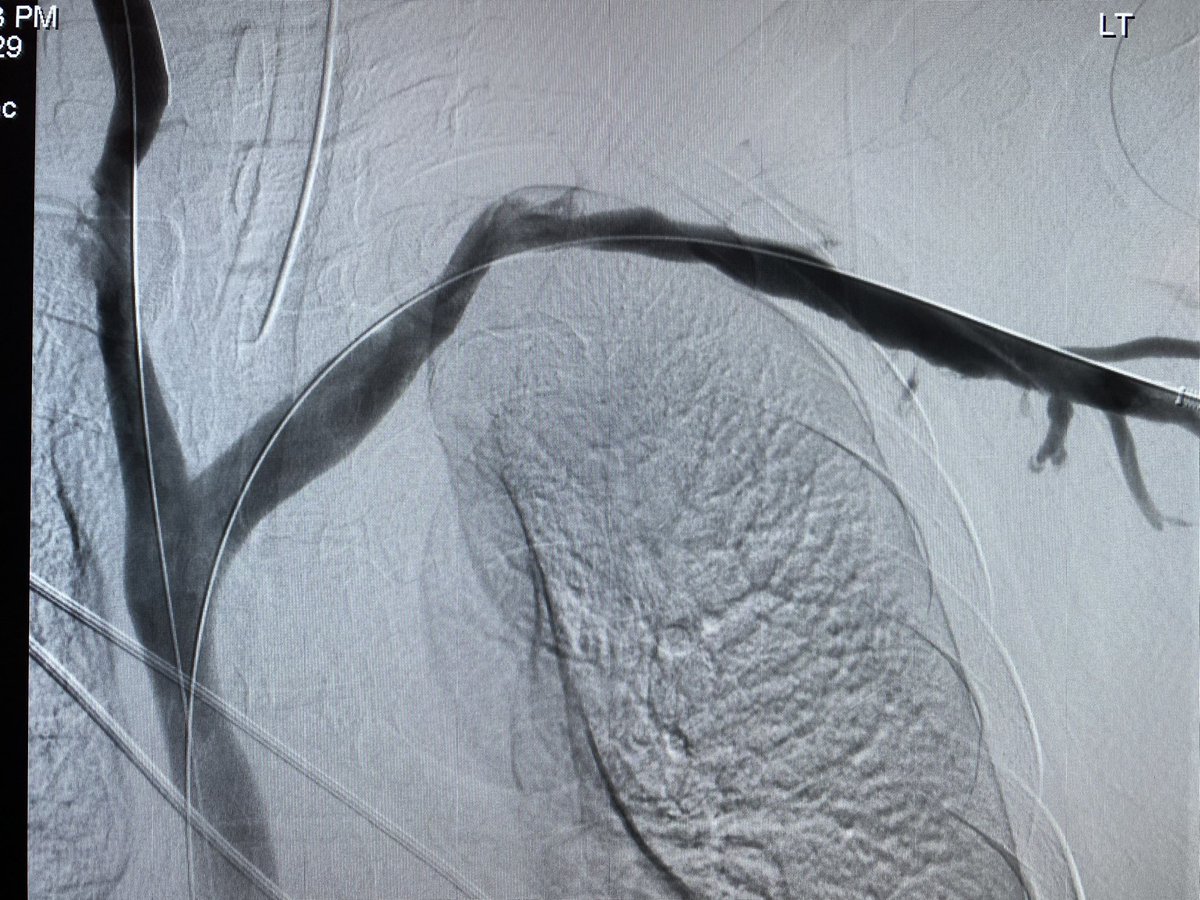

Type 1A endoleak with a short ascending graft and expanding arch. Our team’s first experience using the Bolton Arch graft. Really precise deployment and easy cannulation of the tunnels @TerumoAortic @CAIRweb #aorta